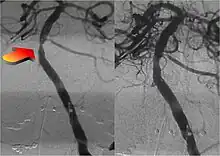

Parallel to the development of catheters, in the radiology and neuroradiology units, image technology dramatically improved: Charles Mistretta in 1979 invented digital subtraction angiography (DSA), the technique currently in use. It consists of performing skull radiography under basic conditions which are then "subtracted" to the image after contrast media injection, to provide an image where only brain vessels are displayed, with great improvement in the diagnostic potential.

Between January and June 2015, five major randomized trials were published in the New England Journal of Medicine (NEJM) with the collaboration of interventional neuroradiologists and stroke neurologists (in the Netherlands,[17] Canada,[18] Australia,[19] US[20] and Spain[21]) regarding the role of mechanical thrombectomy in the treatment of ischemic stroke, demonstrating that if it is performed in centers with proven experience, intra-arterial mechanical thrombectomy is more effective than traditional treatment (intravenous thrombolytic injection). The promising results of these mechanical thrombectomy trials were highlighted by the NEJM in an editorial, which concluded with the statement: "Endovascular equipoise no longer exists. It's about time."[22]

Thrombectomy is currently recommended by the guidelines written by the main American (AHA/ASA)[23] and European (ESO-ESNR-ESMINT)[24] societies of stroke neurologists and interventional neuroradiologists.